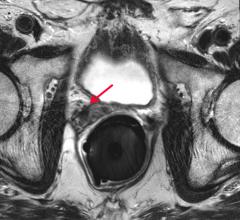

July 1, 2020 — Prostate MRI is an emerging technology used to identify and guide treatment for prostate cancer and has ...